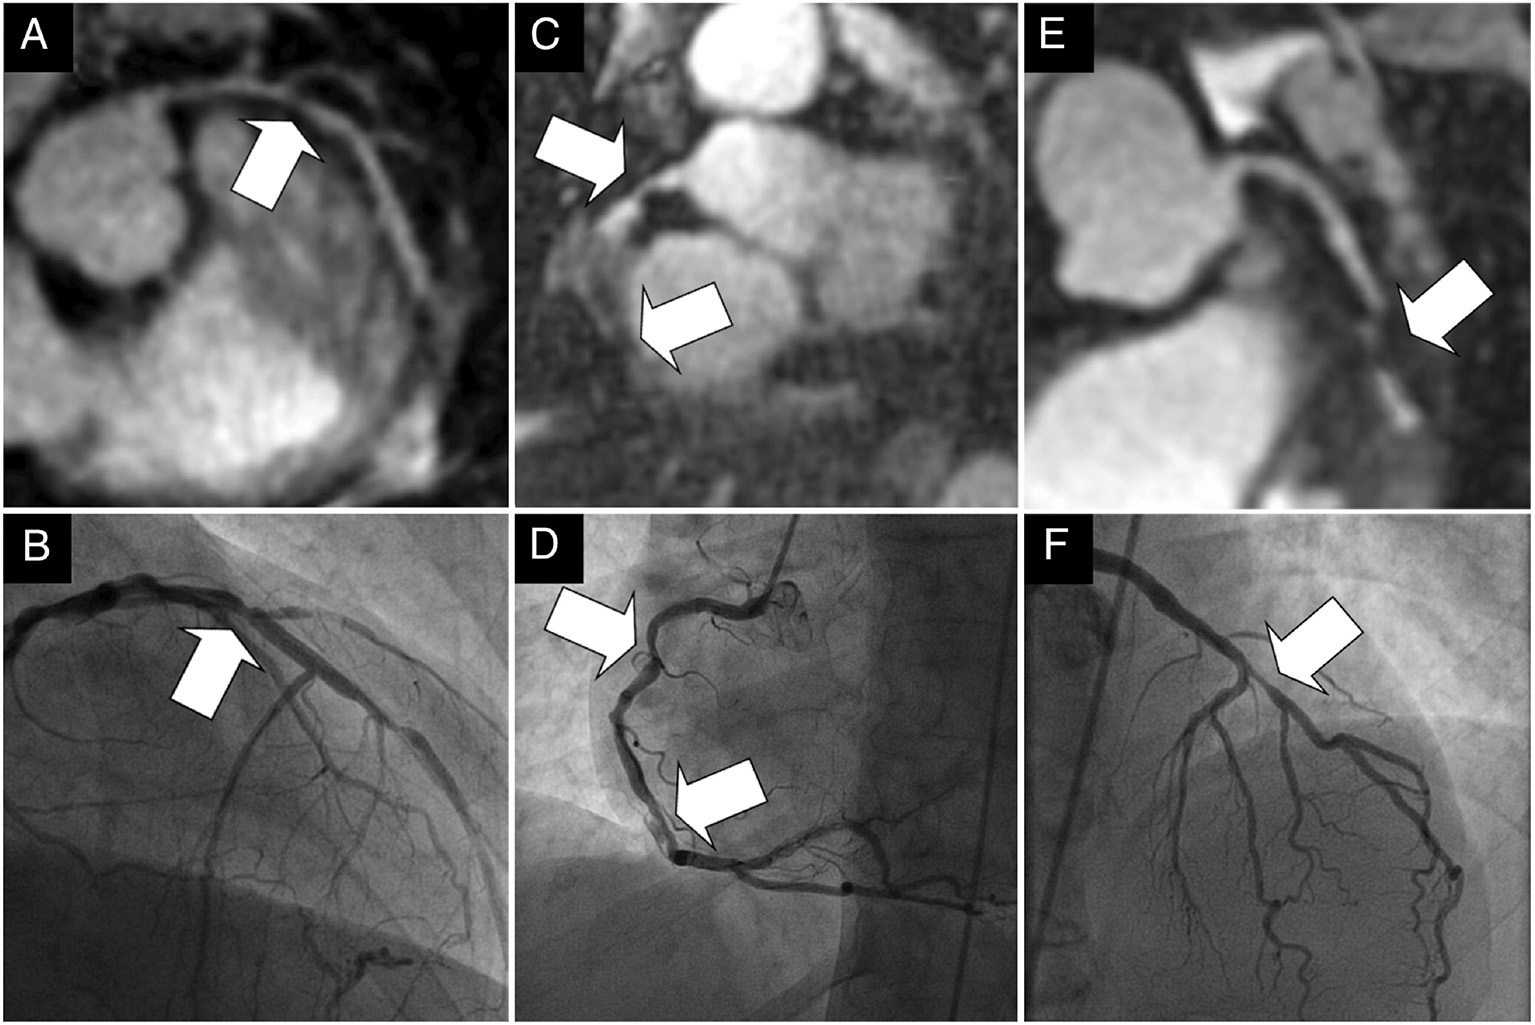

Several novel respiratory motion compensation frameworks have recently been proposed to overcome some of these drawbacks, principally to deal with the 3D nature of respiratory motion, improve image quality, increase respiratory scan efficiency to 100% and therefore significantly reduce acquisition times. Using the so called “1D self-navigation” approach (40), the acquired CMR data is used to estimate displacement/movement of the heart induced by respiratory motion (40, 41), eliminating the need for the correction factor, enabling translational motion correction and acquiring data at every point of the respiratory cycle which enables 100% respiratory scan (42–45). In a cohort of 78 patients, a self-navigated CMRA framework enabled 92, 84, and 56% of proximal, middle and distal coronary segments, respectively, to be visualised, with a per vessel sensitivity and specificity for stenosis (>50%) detection of 65 and 85% compared with X-ray coronary angiography (Figure 1) (46).

Figure 1

(A–F) Examples of the comparison between multiplanar reformats of the whole-heart 1D self-navigated CMRA data sets (top row) and the corresponding x-ray coronary angiograms (bottom row) in three patients. The lesion in the proximal LAD artery and just distal to the take-off of a diagonal branch can clearly be identified in the first patient in (A). while this is confirmed on the x-ray angiogram in (B). While the luminal narrowing of the proximal RCA in the second patient on (C). can clearly be identified, the further course of this artery is obscured in the region of a stent. The same in stent restenoses can be identified in (D). In the third patient in (E). significant disease is identified in the proximal LAD artery at CMRA and is confirmed on, (F). the corresponding x-ray coronary angiogram. Arrows = stenoses; LAD, left anterior descending artery; RCA, right coronary artery. Adapted with permission from Piccini et al. (46).